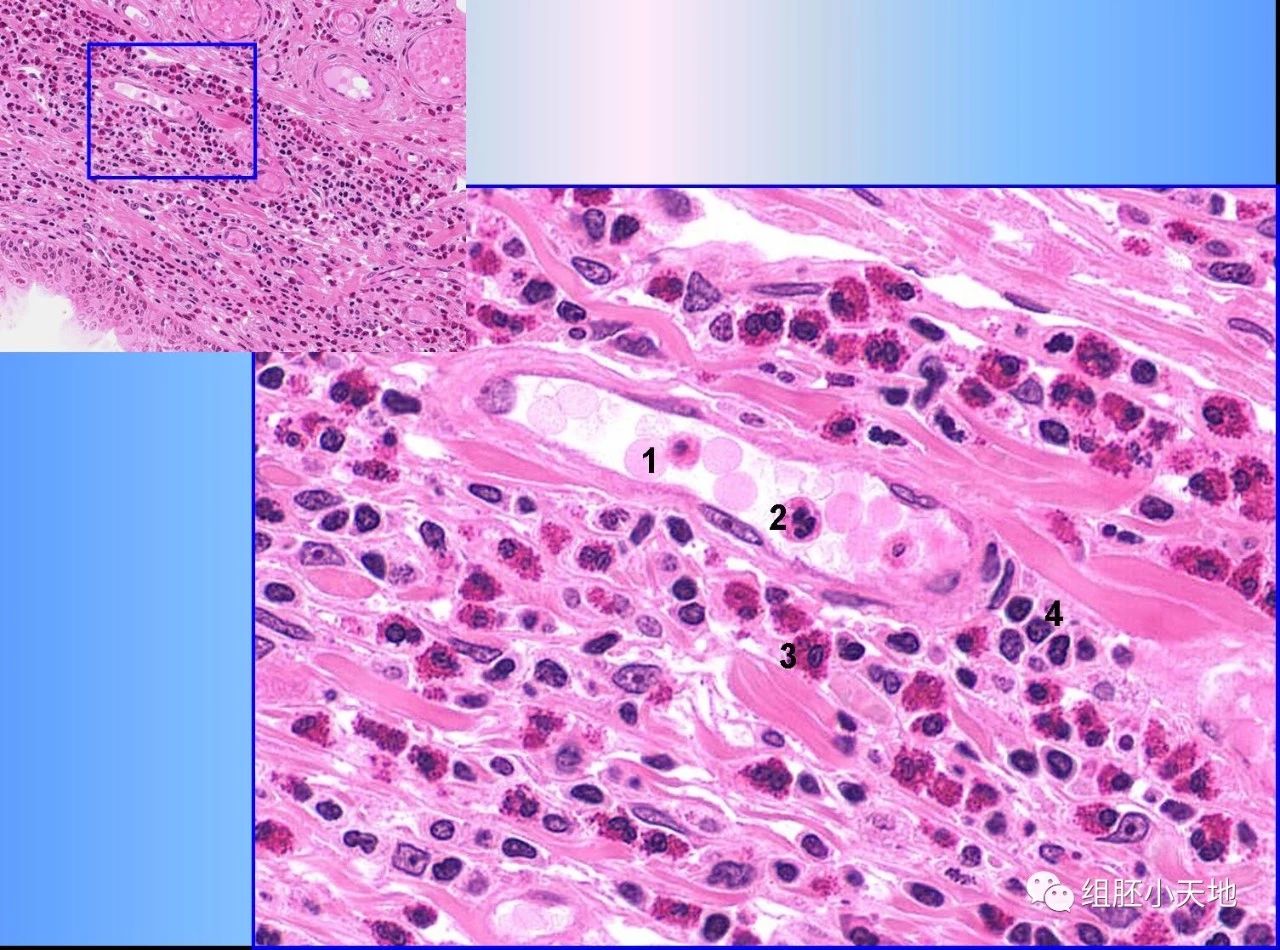

图8. 结缔组织中的白细胞(HE染色)

白细胞要离开血管到组织中发挥作用。图中1示红细胞胞,存在于血管中。2示中性粒细胞(尚未离开血管),可见明显的分叶核,胞质细小粉红色颗粒。3示结缔组织中的嗜酸性粒细胞,细胞核分叶不明显,胞质内见大量均匀的红色颗粒。4示结缔组织中的淋巴细胞,细胞小,核异染色质丰富,染色深。此处结缔组织中有如此多的嗜酸性粒细胞等白细胞,通常是病理表现。